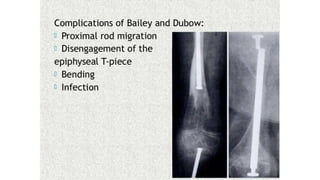

This document discusses a disease and its investigation and management. It begins by introducing Dr. Aniket Wankhede from MGIMS Sevagram and asks what the disease is. It then asks how the disease happens and discusses its causes. Next it asks how the disease appears on x-rays and describes symptoms some people experience living with it. Finally, it asks how the disease will be investigated and managed.